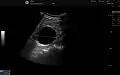

The complex cyst can be further evaluated with doppler ultrasonography, and for Bosniak classification and follow-up of complex cysts, either contrast-enhanced ultrasound (CEUS) or contrast CT is used.[8]

A very small (8 mm) simple renal cyst.